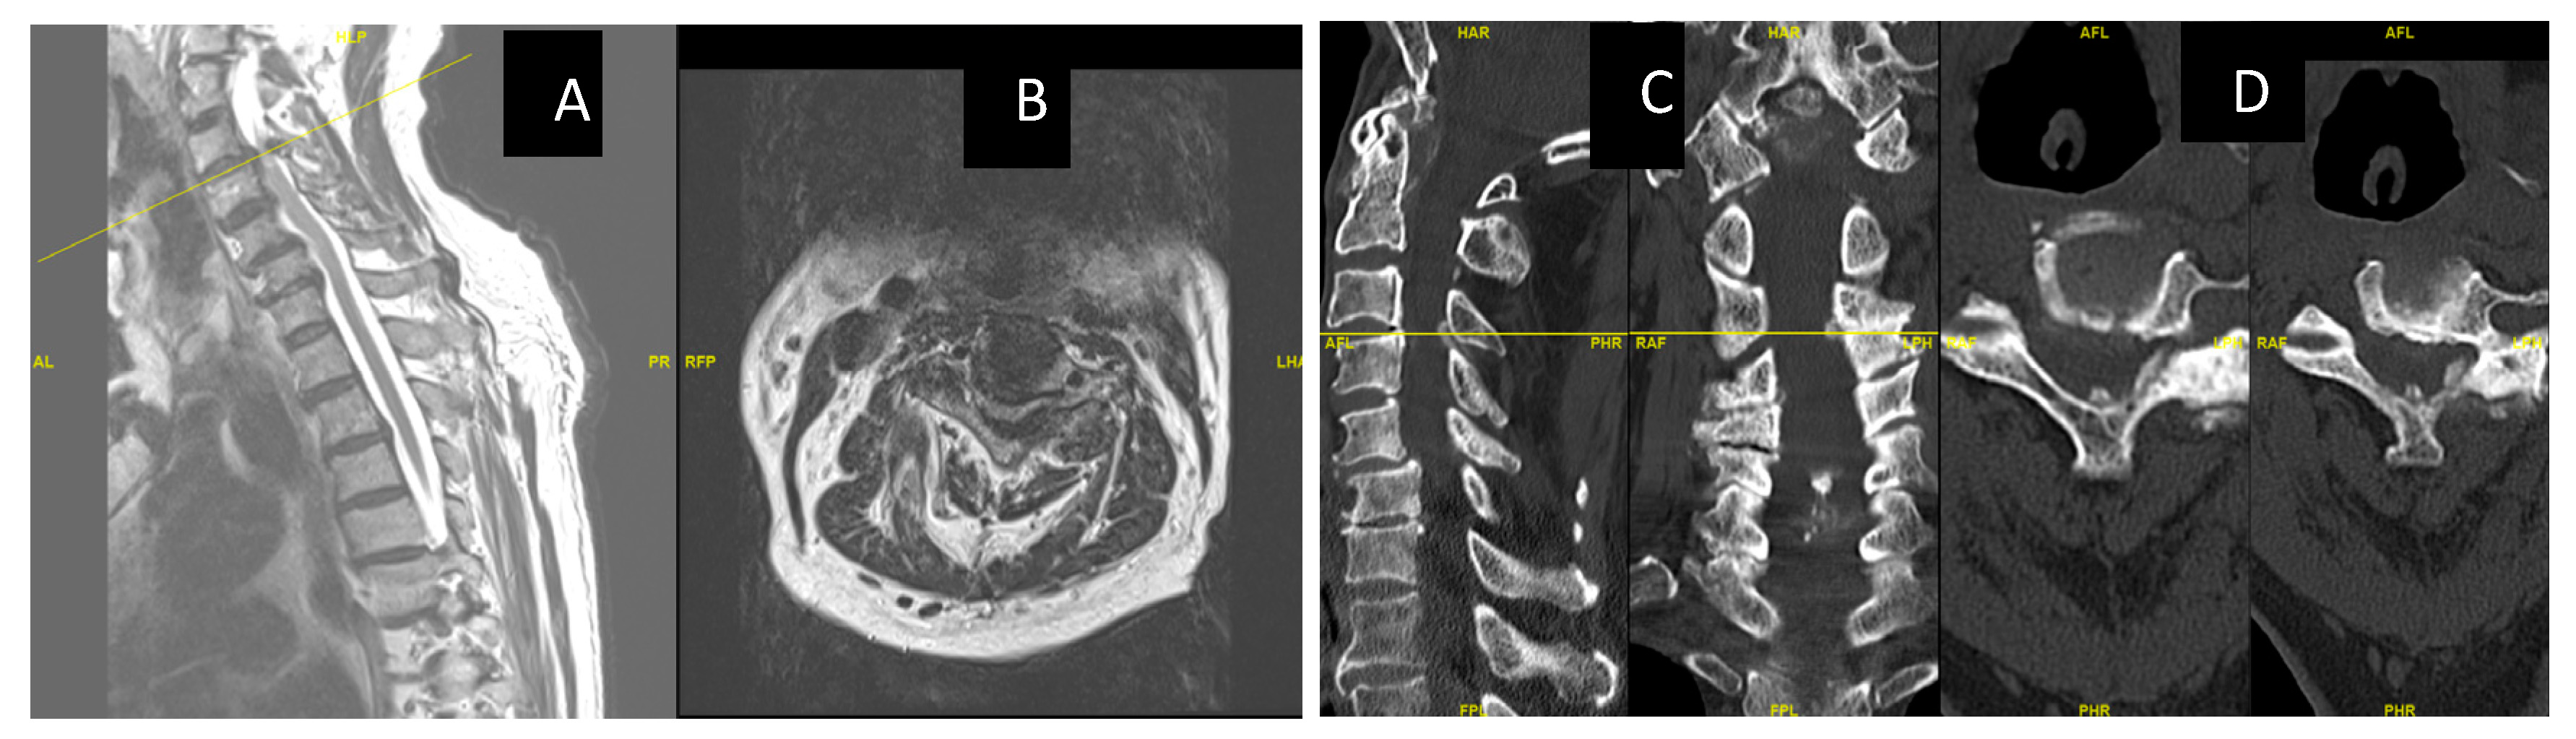

Here, we describe a case of cervical myelopathy with degenerative disc disease and ossified ligamentum flavum at the c3 level (Figure 1A–D).

Figure 1.

(A,B): MRI showing severe central canal and severe bilateral neural foraminal stenosis at C3-4 with compression on the spinal cord and focal gliosis/myelomalacia/ Figure 2 (C,D) show CT images of C34 OLF, C34 and C56 listhesis.